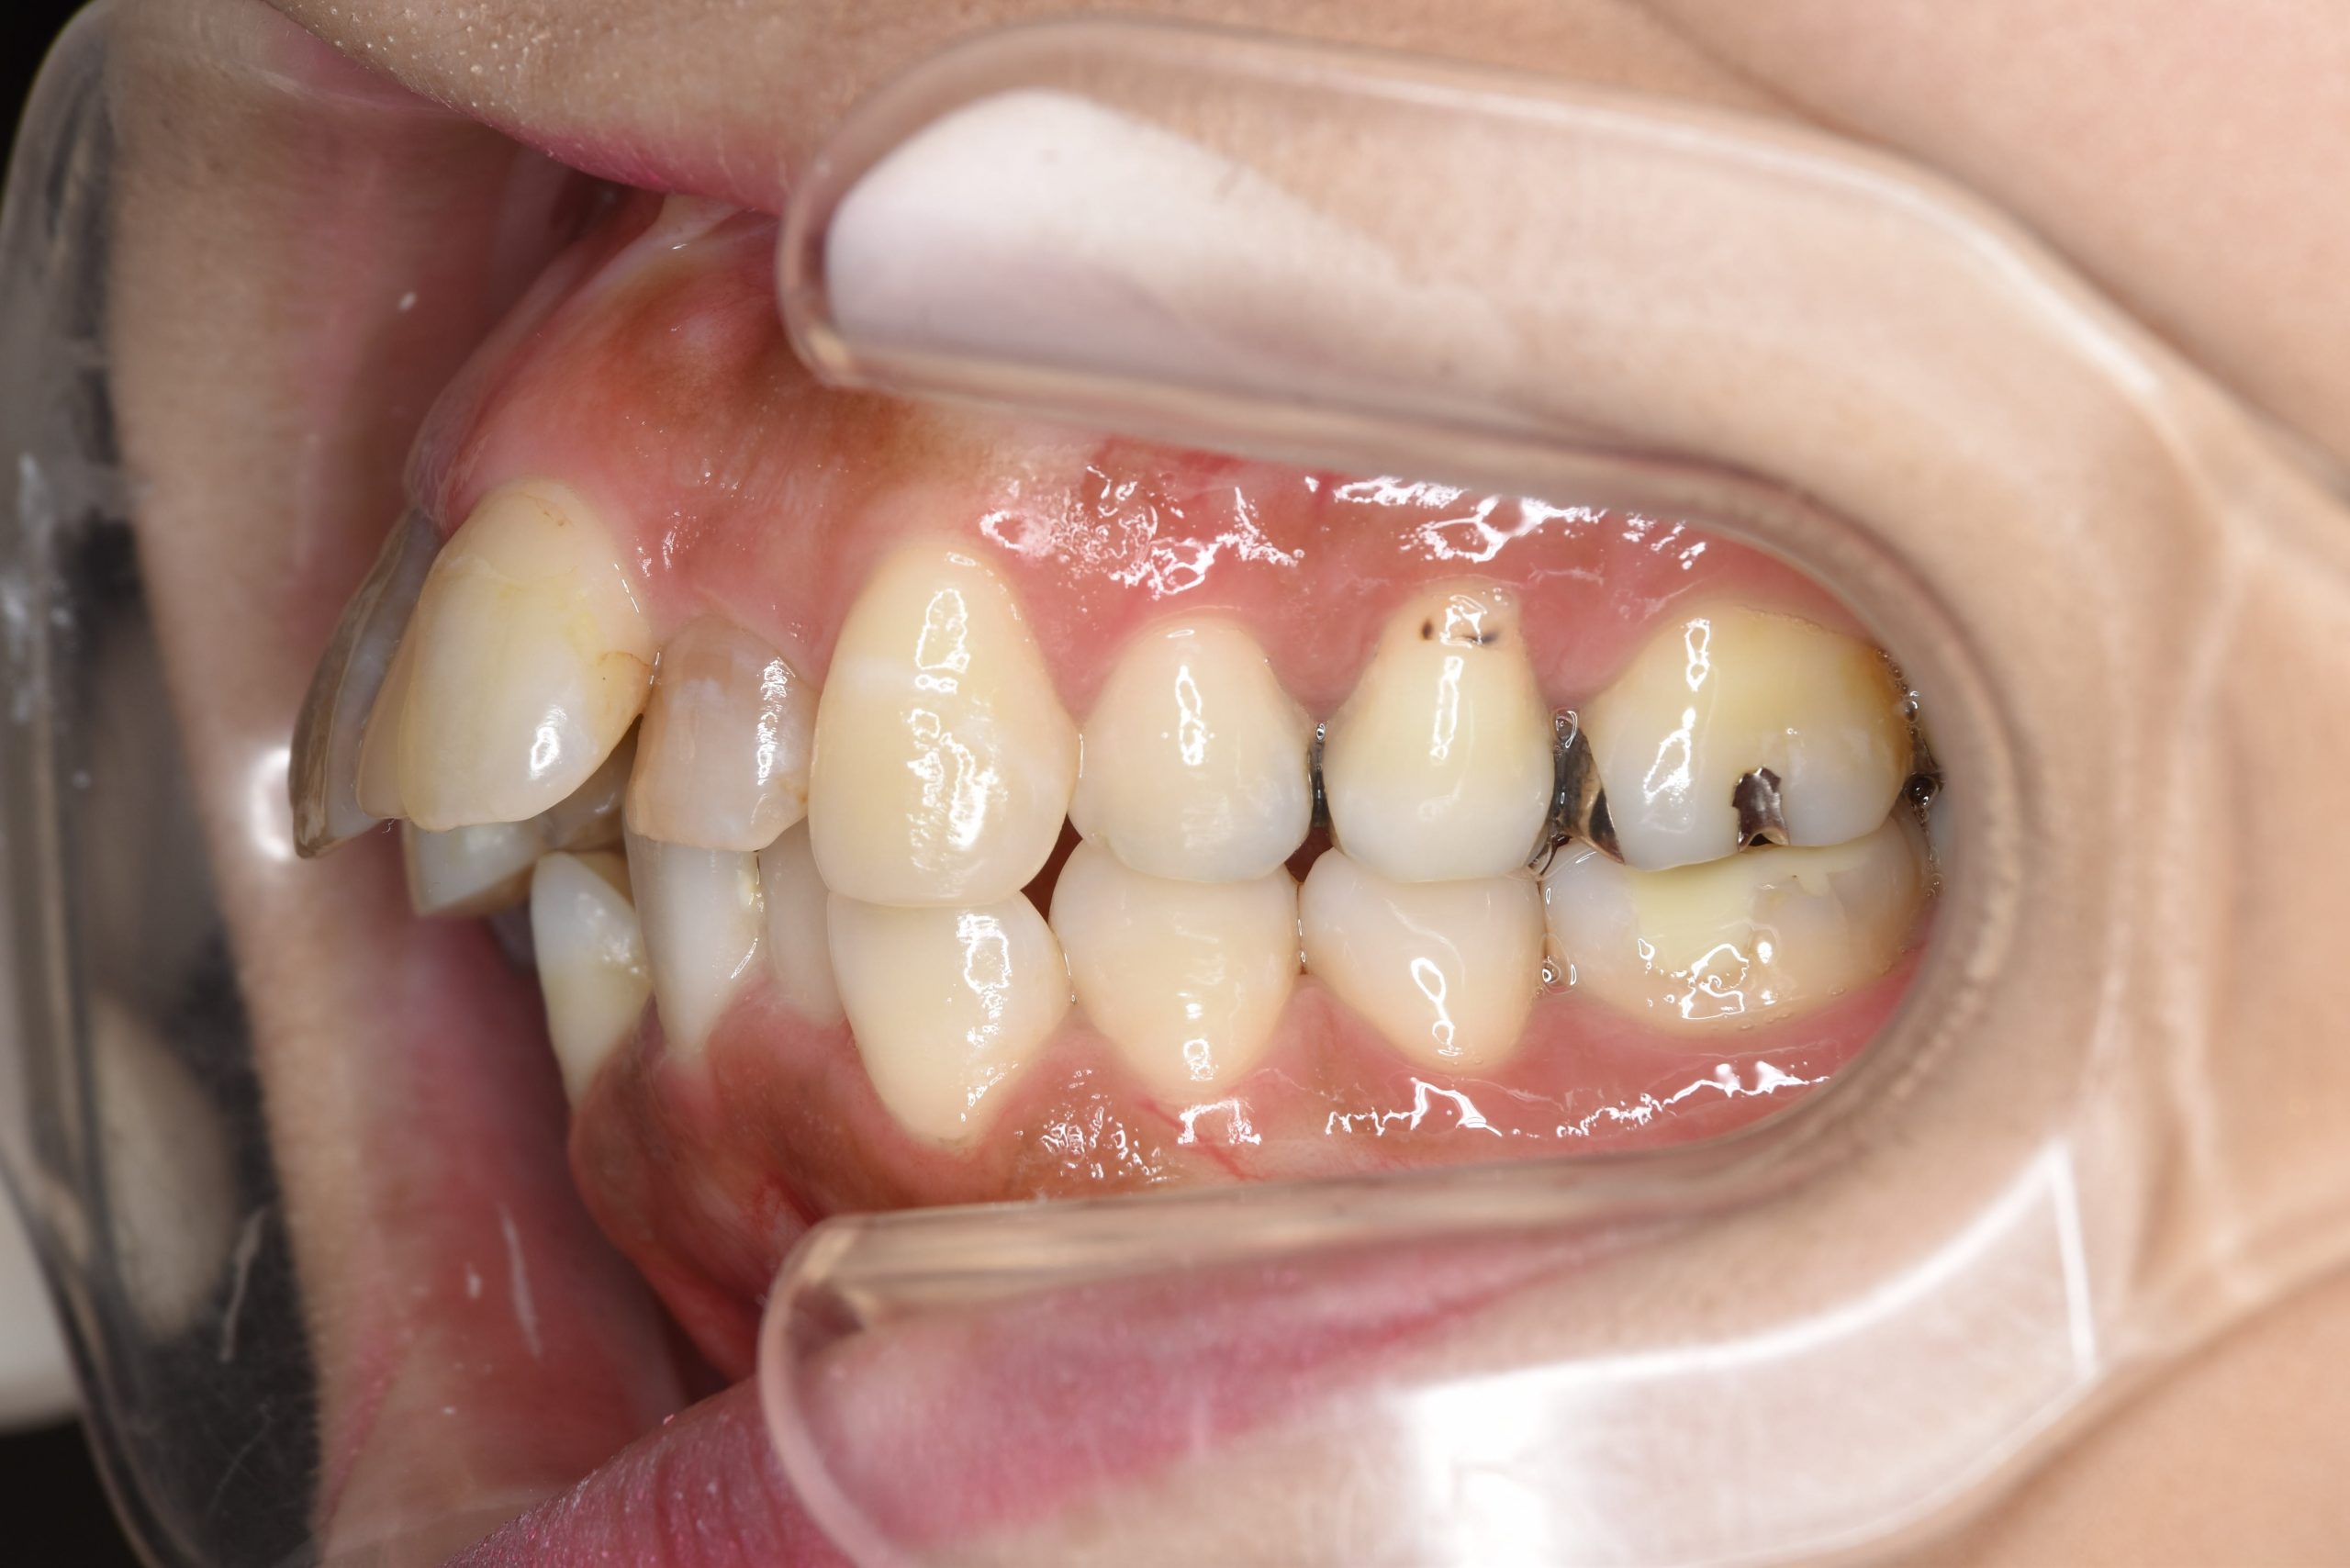

ビフォー

主訴 歯並び|前歯の色|歯ぐき|かみ合わせ

施術内容 成人矯正1期治療

治癒期間 2年5か月間

費用 1,085,700円(税込)

リスク・副作用 違和感、不快感、痛み